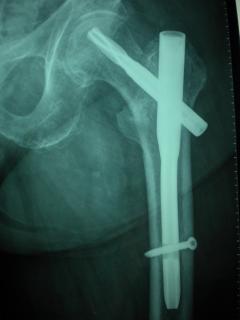

Περίπτωση 2ου ασθενούς

Με τα σύγχρονα μέσα που διαθέτουμε, όλα σχεδόν αυτά τα κατάγματα πρέπει να αντιμετωπίζονται χειρουργικώς. Υπάρχει πληθώρα υλικών οστεοσύνθεσης (πλάκες διαφόρων τύπων, ενδομυελικοί ήλοι, συστήματα εξωτερικής οστεοσύνθεσης) που είναι διαθέσιμα και επαφίεται στην εμπειρία του χειρουργού η επιλογή.

Οπως και άλλοι εξοικειωμένοι χειρουργοί διεθνώς, χρησιμοποιώ τεχνικές ελάχιστης παρέμβασης (Minimal Invasive Surgery), δηλαδή μικρές τομές, επειδή έτσι το χειρουργικό τραύμα είναι ελάχιστο, με αποτέλεσμα ταχύτερη επούλωση. Ταχύτερη πώρωση των καταγμάτων, ταχύτερη κινητοποίηση.

Όλες οι φωτογραφίες ολες προέρχονται από το προσωπικό αρχείο του κου Μ. Τυλλιανάκη